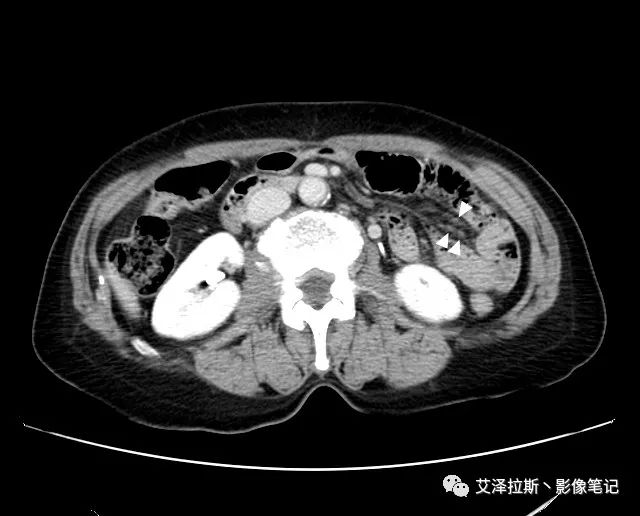

圖1 平掃+增強各期

【影像所見】 胃竇部狹窄,胃壁環形增厚,小彎側見一巨大潰瘍,周圍伴“環堤征”,漿膜面不完整,胃周脂肪見網格狀條索影,病灶與肝臟左葉、胰腺鉤突脂肪間隙消失,增強掃描病灶明顯強化。引流區內約15個區域淋巴結受累。

【診斷意見】 胃竇部胃癌(T4N3期) 該病例腫塊突破漿膜層,與肝臟左葉、胰腺鉤突分界不清,脂肪界面消失,定為T4期; 受累及的淋巴結為15個區域,定為N3; 有無遠處轉移尚不明確,所以M期暫時無法確定。